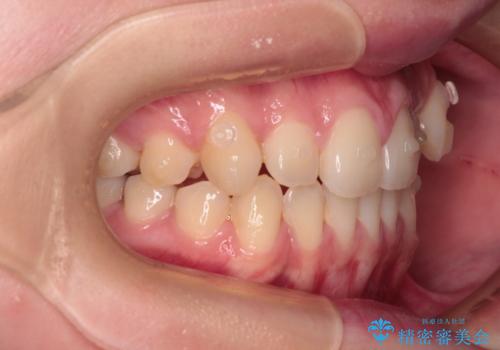

- 左右の八重歯を気にして来院された患者様です。

歯列としてはインビザラインでもワイヤー矯正でも対応できるものでしたが、インビザラインによる治療を希望されていました。

上顎の八重歯改善にインビザラインでは時間のかかってしまう可能性があり、更には口元が治療前よりも突出してしまう可能性があったため、補助装置により八重歯を事前に引き込んでおくことで、インビザラインによる治療をスムーズに行えるように計画しました。